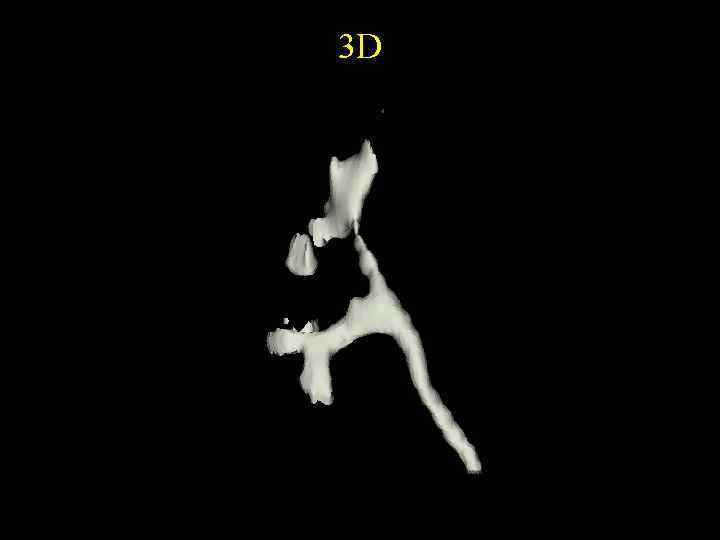

3 D